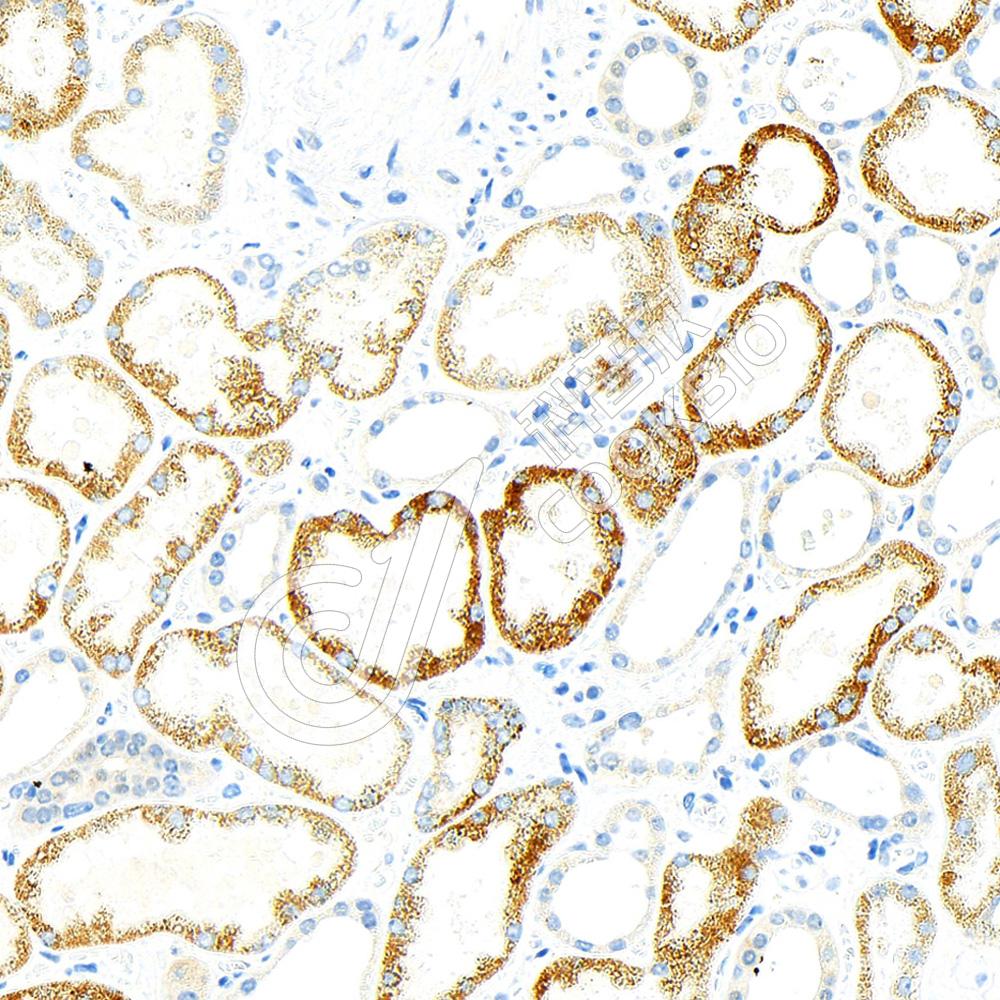

IHC检测AMACR蛋白(货号 K5453585).

样品: 人肾, 4%多聚甲醛 (货号KSG1101) 固定12-24小时.

抗原修复: 柠檬酸抗原修复液(干粉, pH 6.0) (KSG1201), 高压锅均匀喷气计时2分钟.

—抗: 1: 600稀释, 4℃ 孵育过夜.

二抗: S-vision免疫组化多聚二抗(山羊抗小鼠), 即用型(货号KB3903), 室温孵育20分钟.